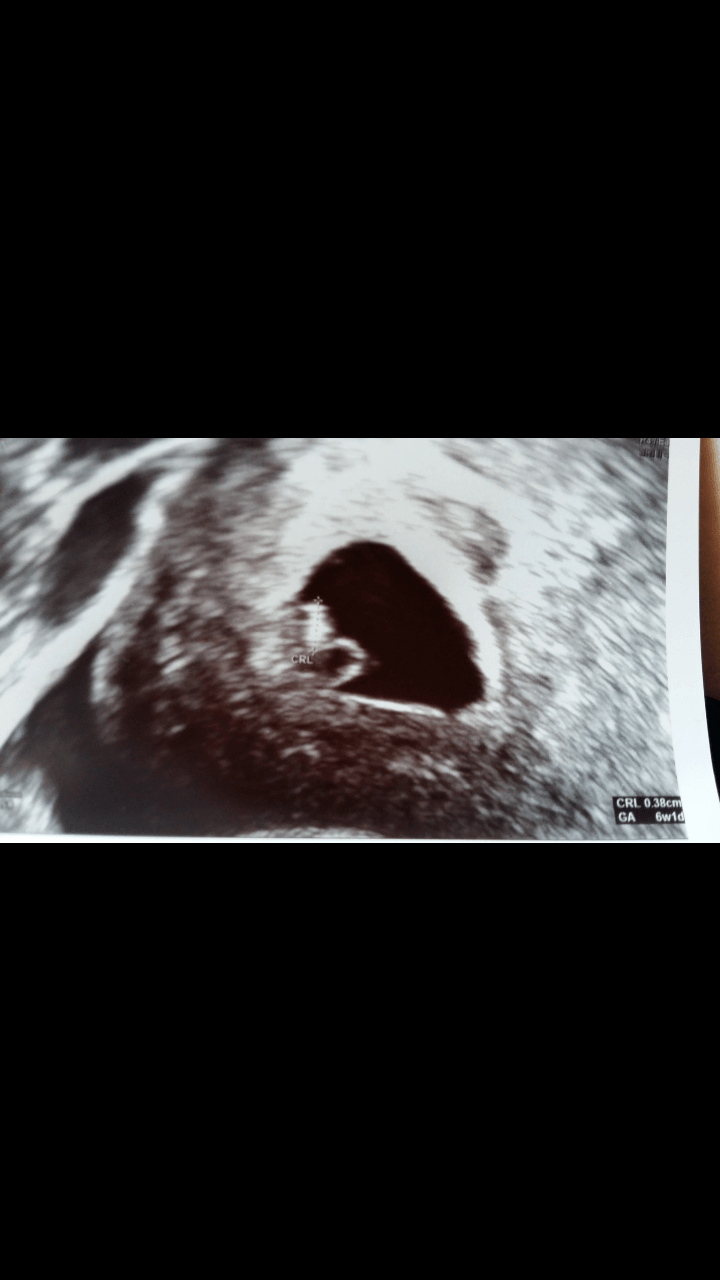

Byłam dzisiaj na USG i wszystko jest w porządku. Fasola ma 3,8 mm, serduszko bije. Ale mi ulżyło! Wg USG to 6 tydz 1 dzień i termin na 22 lutego.

Fasolka: